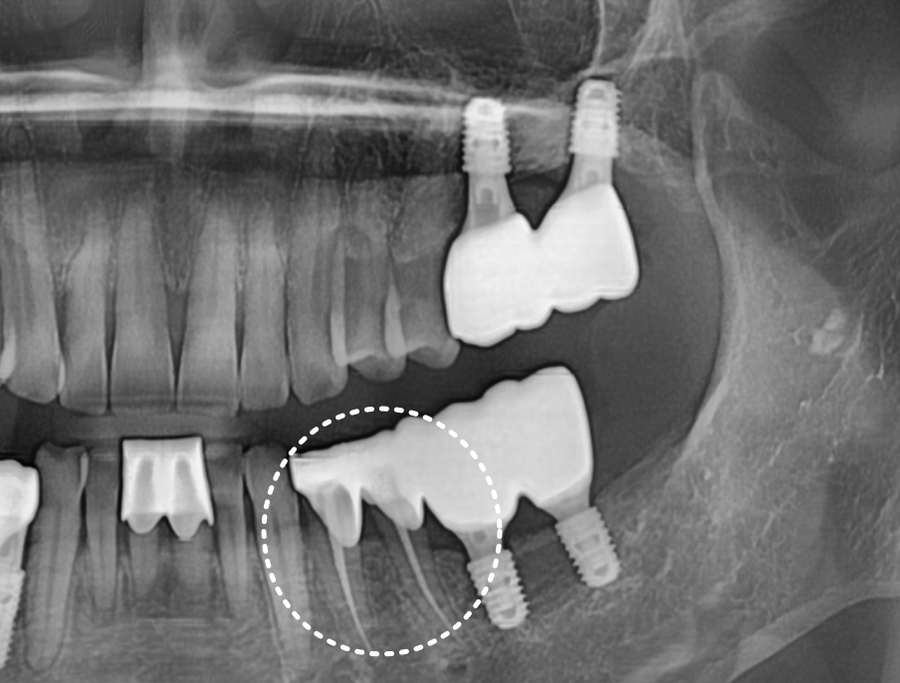

고덕동 치과 230926 왼쪽 아래 어금니 2개 치료

저희 치과에서 왼쪽 아래 어금니 임플란트를 하신

60대 여성 환자분이십니다.

250321

1년 반이라는 시간이 꽤 길었던 건지

이미 충치가 많이 커진 상태였어요.

1년 반 전 엑스레이 사진과 그 후 사진입니다.

충치 크기 차이가 꽤 많이 나죠?

이미 신경까지 침범한 충치로 인해

신경치료를 결정할 수밖에 없었습니다.

250717 신경치료 후 크라운으로 마무리한 모습

신경치료 후, 약해진 치아가 깨지는 것을 방지하기 위해 크라운까지 씌워 치료가 마무리되었습니다.